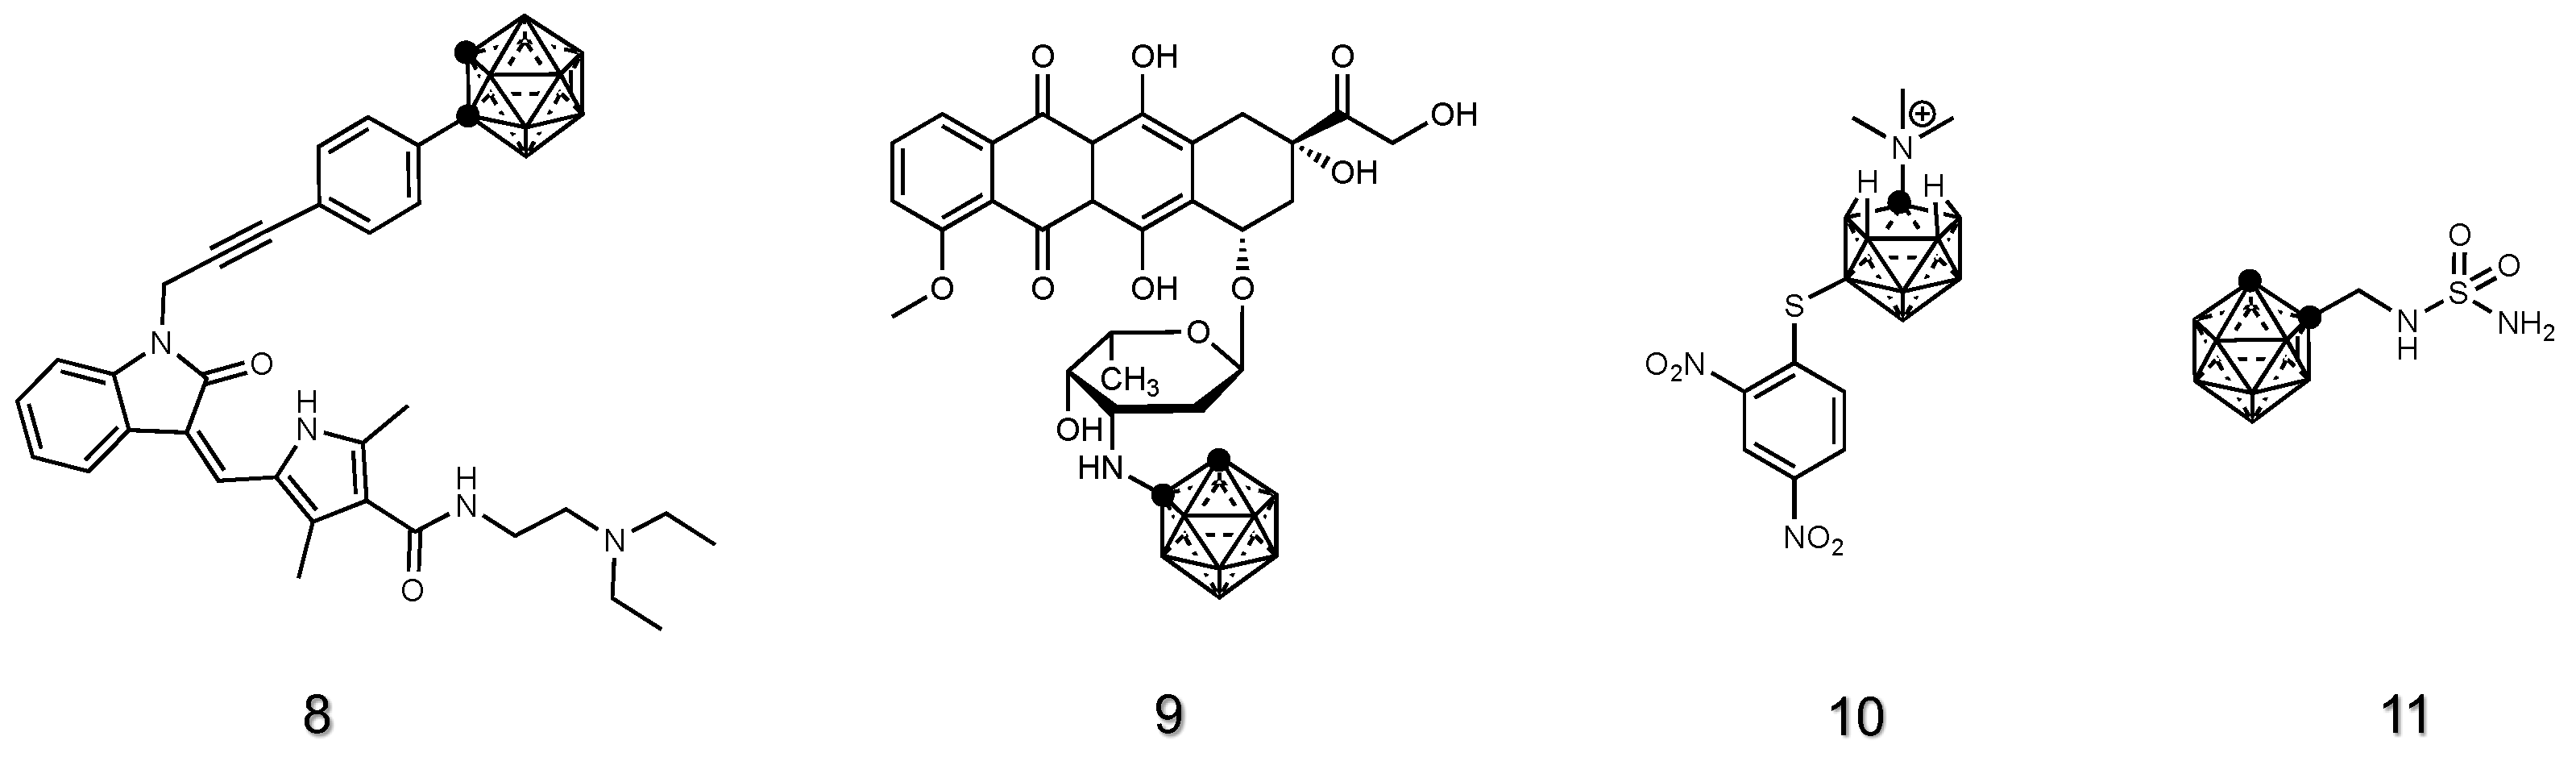

2.1.3. Drug Derivatives of Carboranes

2.1.4. Porphyrin Derivatives of Carboranes

2.1.6. Amino Acid Derivatives of Carboranes